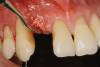

Fig 10. Clinical application of i-PRF: red i-PRF for coating implant surface.

Figure 10